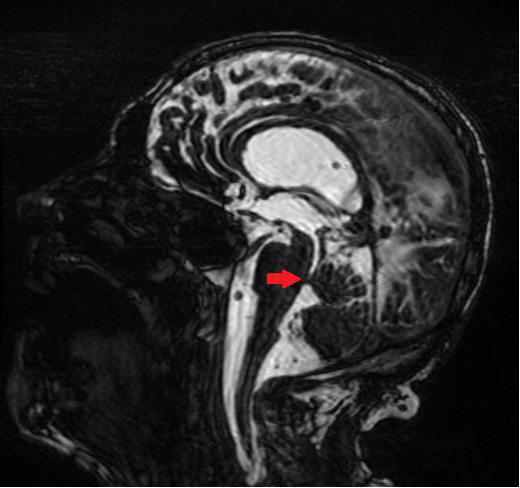

Hydrocephalus Due to Neurocysticercosis in the Cerebral Aqueduct: Case Report

Felipe Meireles Dória, Lívia Novaes Teixeira, Matheus Costa Freitas, Isabella Versiani Martins Rocha, Raquel Cordeiro Mendes, Bárbara Bastelli

bjcr148